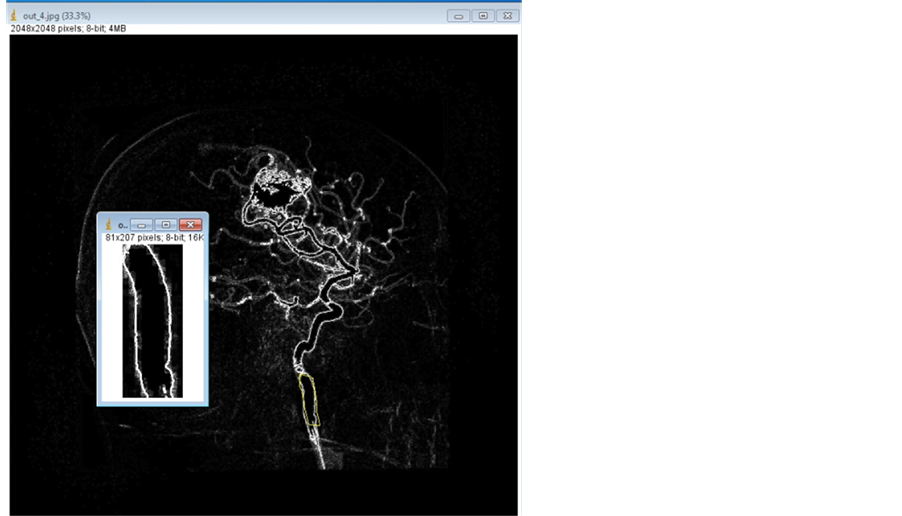

This section describes method for segmenting the Digital Subtraction Angiogram (DSA) images. The data is obtained from KMC Manipal. The input image is preprocessed using Gaussian noise and Hessian matrix based filtering is applied to angiogram images, to detect the tubular structures of vessels using eigenvalues [5] . Figure 2 shows adaptive segmentation technique methodology. The preprocessed image is segmented using OTSU segmentation to create an initial vessel segment as shown in Figure 3. The length and diameter of vessel is calculated using the ROI tools on the vessel segment [6] [7] . The diameter of the initial part of segmented region set as reference node-P1. The diameter is calculated for every small change of the vessel. The sub segment of vessel is created, whenever there is an increase of 10% of diameter of newer segment more than reference diameter, which is shown as segment-P2 as shown in Figure 4. The entire vessel is segmented into smaller sub- structures for variation in diameter with comparison to reference diameter. This is repeated for entire vessel structure. This leads to different combinations of sub-segments of vessels.

Figure 2. Adaptive segmentation technique.

Figure 3. ROI segmentation image.

The adaptive segmentation of threshold based adaptive segmentation for CAVM patients is implemented using MATLAB. Figure 5 shows various segment sub-division based on the threshold factor. The adaptive segmentation using 5% produces more sub-segment and with more accurate in hemodynamics measurements. Twenty-three CAVM patients with 150 different vessel location of DSA datasets were studied as part of the adaptive modeling and 30 simulated data are created with equivalent complexity of DSA, has been evaluated for more than 150 vessels locations for sub-segmentation of vessels.

Figure 5. Adaptive threshold―10 and 5 percentage vessels segments. Source: KMC Manipal.